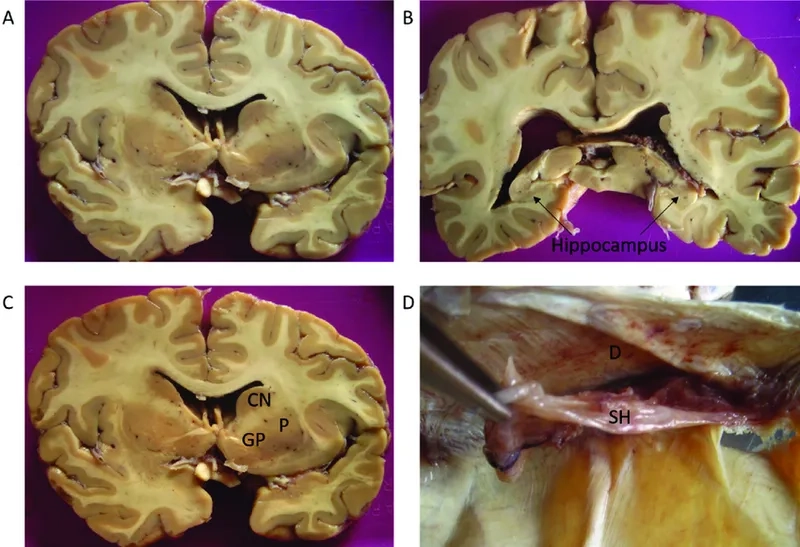

- The accumulation of an abnormal protein called tau forms clumps that slowly spread throughout the brain, killing brain cells and leading to progressive decline.

- As the disease progresses, cognitive impairment becomes more pronounced, with individuals experiencing significant memory loss, confusion, and impaired judgment, which can resemble Alzheimer's disease.

Visualizing concepts related to CTE